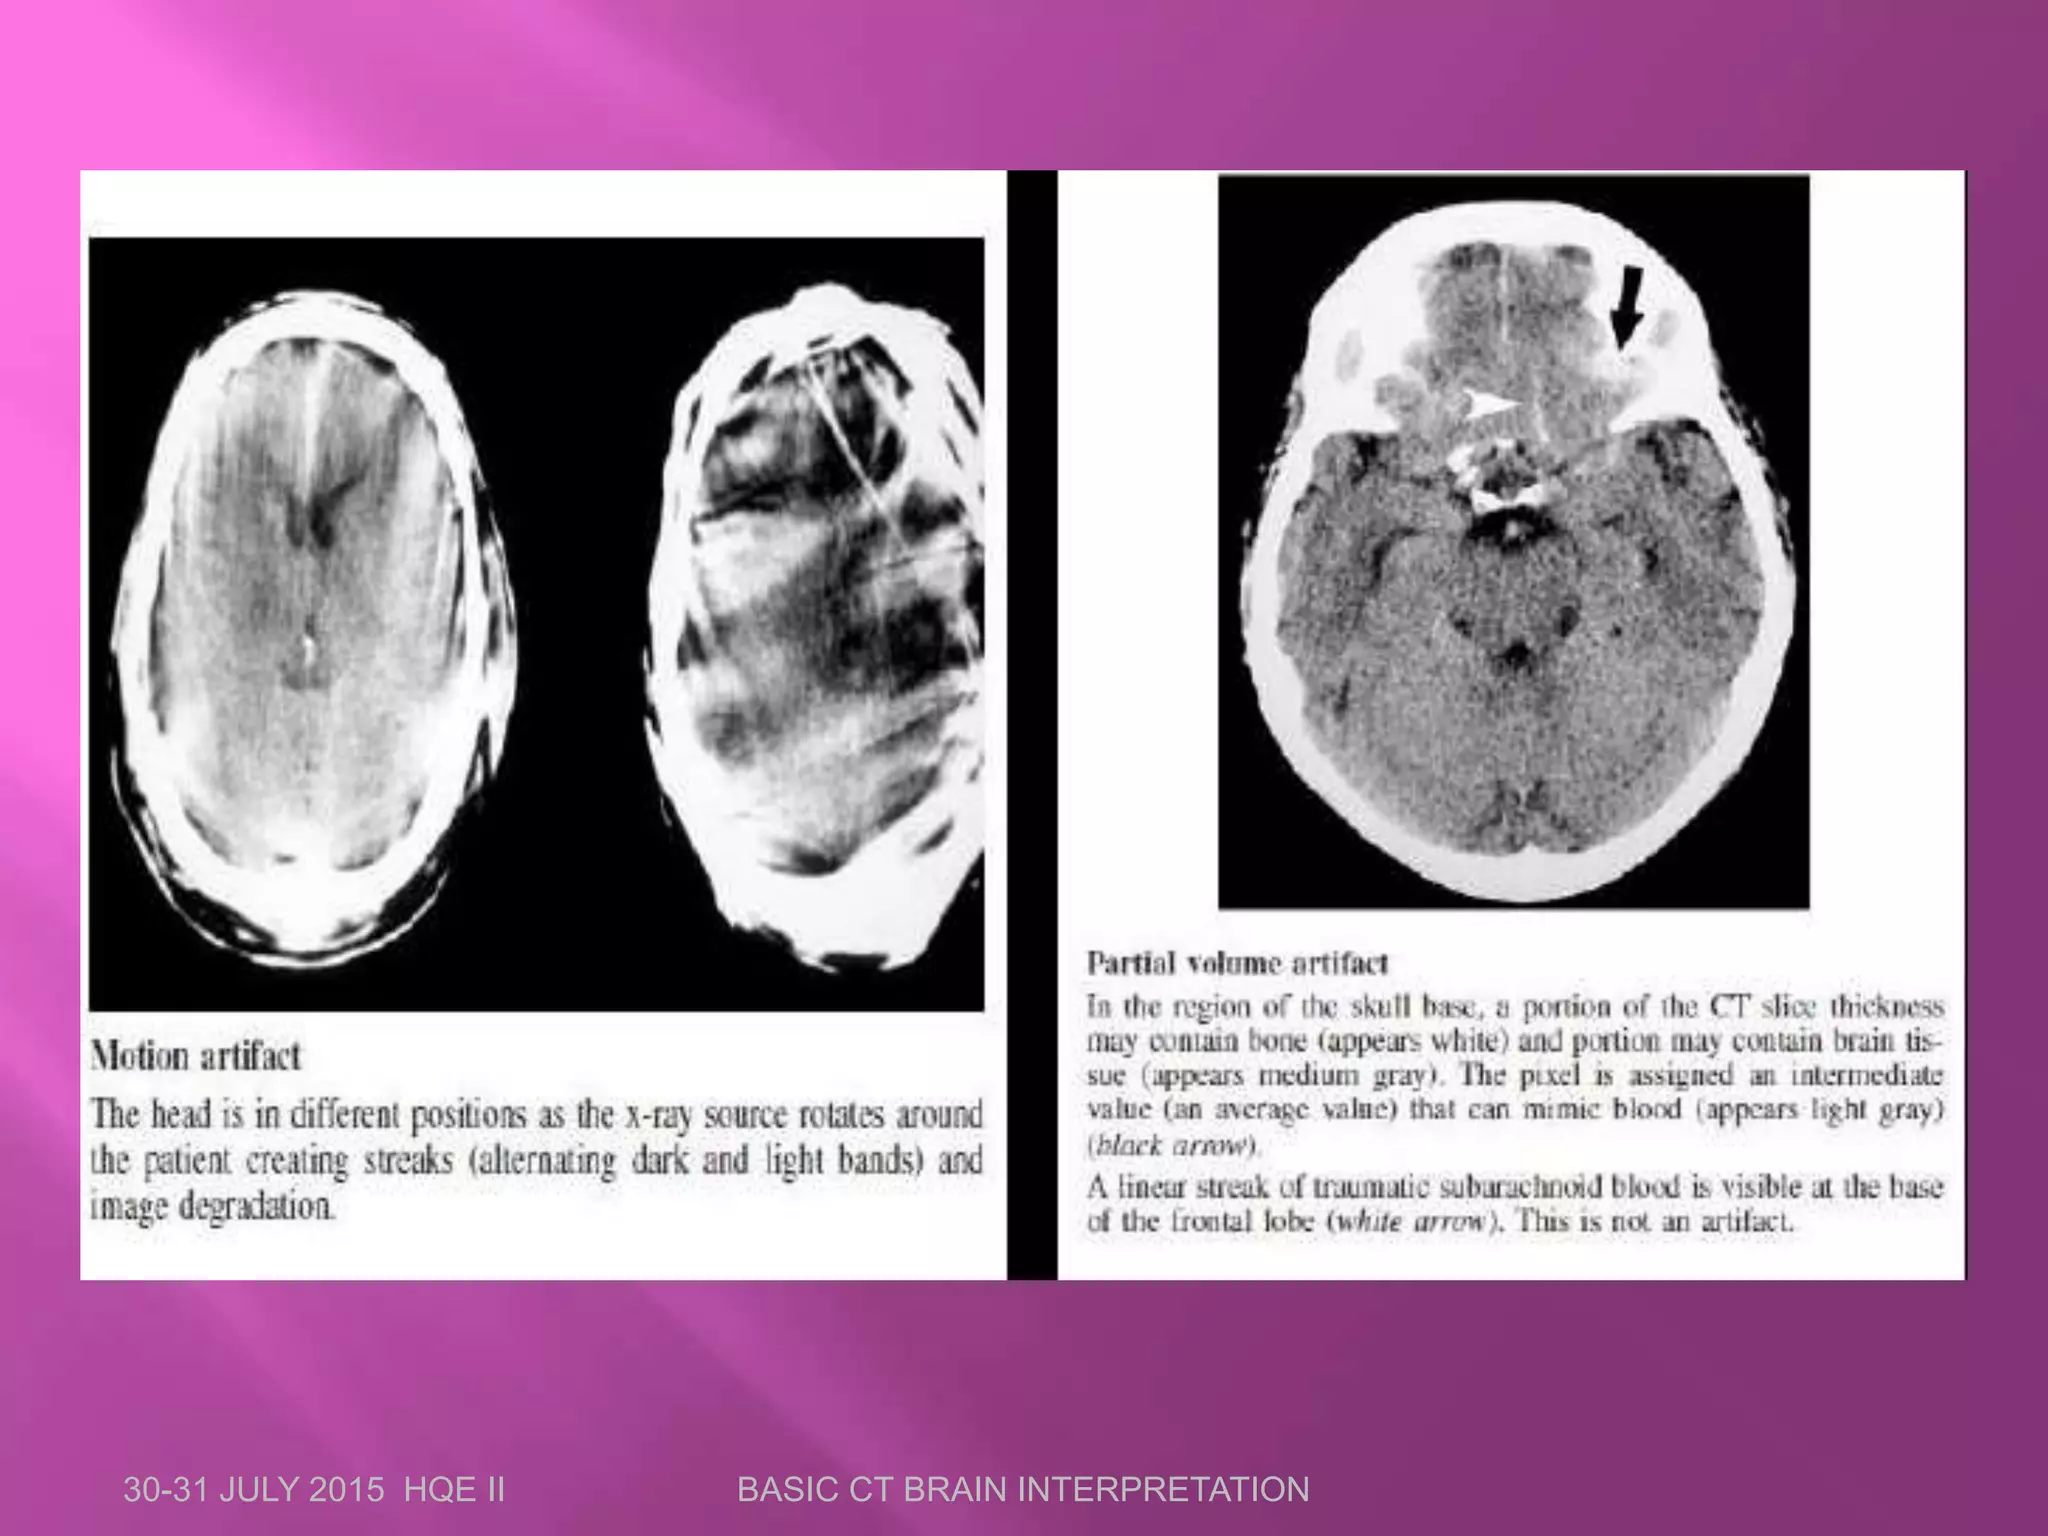

 Artifacts are distortions or errors in the image

that are unrelated to the object scanned.

 Most common artifacts in CT are:

 Motion artifacts

 Streak artifacts

 Beam hardening artifacts

 Partial voluming artifacts

 Ring artifacts